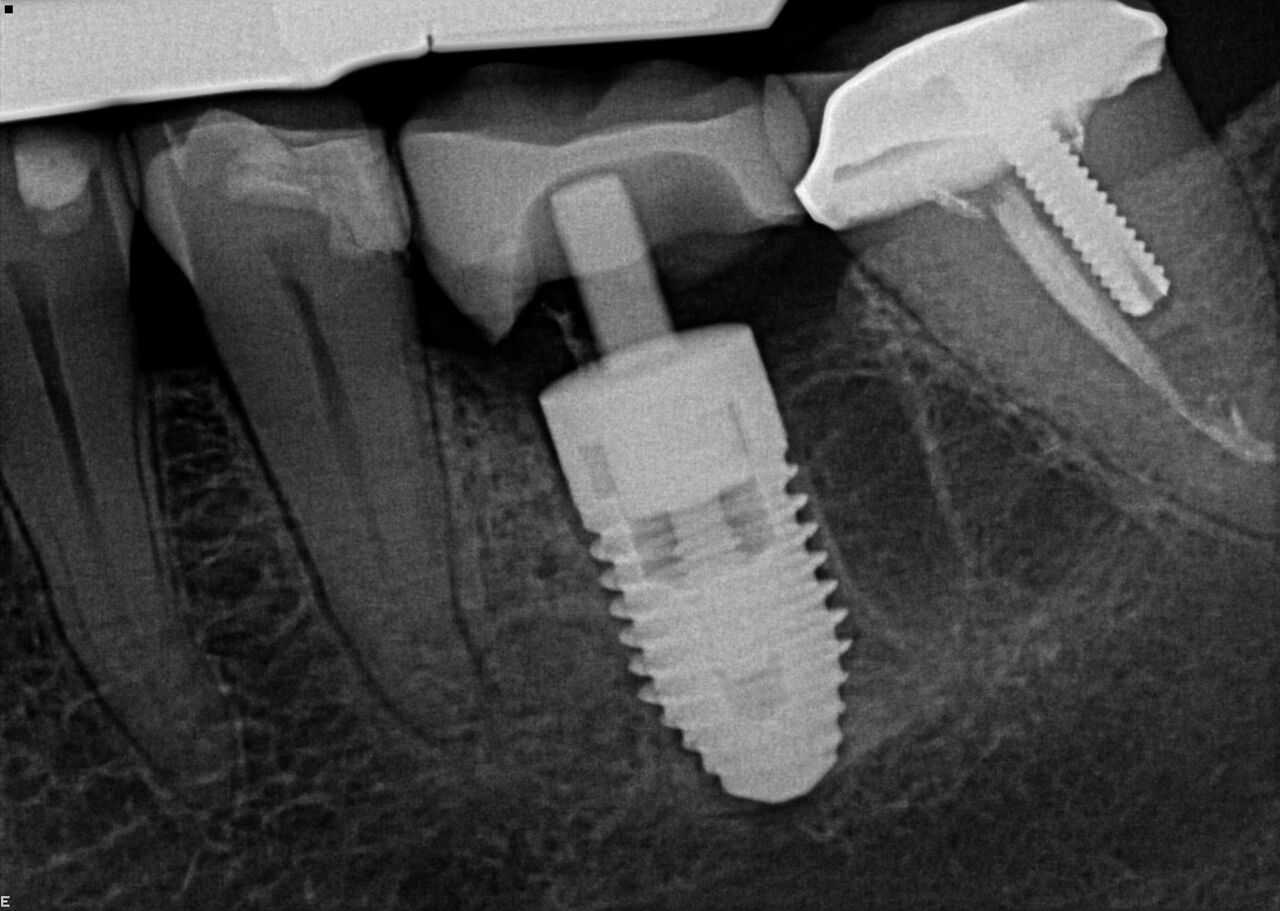

(17.) Case 3 initial radiograph of bridge on Nos. 6 through 9 and crown on No. 10.

Figure 17

(18.) Case 3 initial radiograph of bridge on Nos. 6 through 9 and crown on No. 10.

Figure 18

(20.) 6-month integration confirmation of Nos. 6 through 10.

Figure 20

(21.) 6-month integration confirmation of Nos. 6 through 10.

Figure 21

A 42-year-old man presented with a very loose bridge on Nos. 6 through 9 with periodontally compromised retainers on Nos. 6 and 9 (Figure 17 through Figure 19), and endodontically involved No. 10 with a calcified canal. Teeth Nos. 6, 9, and 10 were extracted, the sockets fully debrided, and pontic soft tissue on Nos. 7 and 8 sculpted to be symmetrical in soft tissue contour with the contralateral lateral incisor and central incisor locations. Implants were secured in position Nos. 6 through 10 (Figure 20) in excess of 45 Ncm, the bone was milled to provide unimpeded seating of temporary abutments, and temporary crowns were fabricated chairside and adjusted to be out of occlusion in centric relation and all excursions. The temporary crowns were cemented after extrusion of excess cement extraorally and the patient was prescribed antibiotics, analgesics, and instructed in postoperative care particular to immediately provisionally restored implants. At 6 months, integration was confirmed (Figure 20 through Figure 23) and after placement of scanning abutments, the implants and soft tissues were scanned. Final crowns were fabricated from the scanned images and were cemented after extrusion of excess cement extraorally (Figure 24 through Figure 26), and oral hygiene procedures were reviewed.